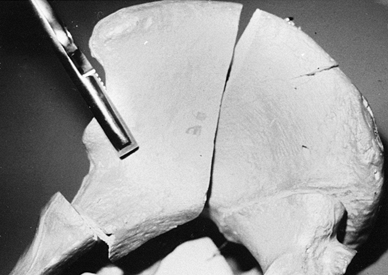

Posterior wall fractures typically

disrupt the posterior rim of the acetabulum, a portion of the

retroacetabular surface, and a segment of the articular cartilage (28).

Instability of the hip (subluxation or dislocation of the femoral head)

can be associated with this fracture pattern. Marginal impaction of the

articular cartilage commonly occurs and should be diagnosed

preoperatively on plain films or CT scan (Fig. 18.3) (3).

Marginal impaction of the articular suface and underlying cancellous

bone occurs when the femoral head subluxes into a displaced major

fracture line. The articular

P.590

surface

of the edge of the major fracture line is displaced secondary to

impaction of the underlying cancellous bone, with malrotation of the

overlying articular surface. In Figure 18.3,

marginal impaction is noted as a change in the radius of curvature of

the articular surface. It is important for surgeons to recognize this

radiographic feature of articular displacement so that they can correct

the displacement. Complex posterior wall fractures can involve the

entire retroacetabular surface and include a portion of the greater or

lesser sciatic notch and the ischial tuberosity. The ilioischial line

remains intact on the AP view (Fig. 18.4A).